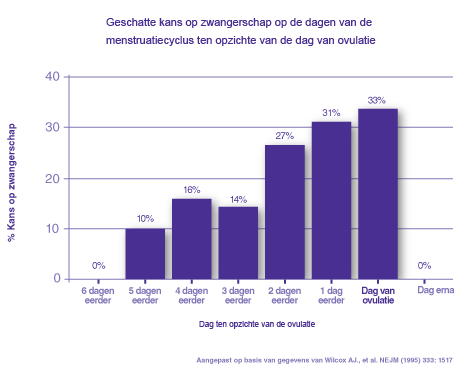

Check Statistieken Over De Tijd Tot Bevruchting

Check Statistieken Over De Tijd Tot Bevruchting

Je Maandelijkse Kans Om Zwanger Te Worden Alweer Een Nieuwe Moeder Blog Persoonlijk Mamablog